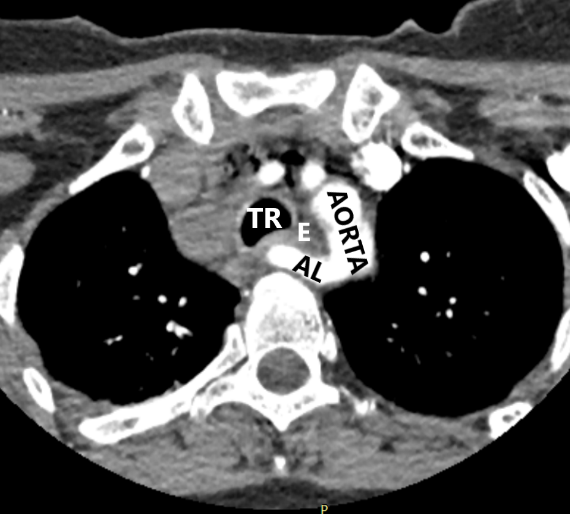

- Правая общая сонная артерия является первой ветвью дуги аорты. Двум пациенткам удалось проследить правую общую сонную артерию до дуги аорты. При этом БЦС отсутствовал. Можно также отметить, что обе пациентки были молодого возраста и без ожирения, что, вероятно, позволило проследить ход артерии до ее устья (рис. 2).

- На уровне правого грудино-ключичного сочленения AL и правая общая сонная артерия располагаются отдаленно друг от друга. Данная сонографическая картина выявлена у всех 4 пациенток (рис. 3).

- На уровне правого грудино-ключичного сочленения AL и правая общая сонная артерия располагаются перпендикулярно друг к другу. Данный признак выявлен у всех пациенток (рис. 4).

Рис. 2. Пациентка 32 лет, индекс массы тела (ИМТ) – 18,5. а – УЗИ сосудов верхнего средостения конвексным датчиком в В-режиме (цветное дуплексное сканирование менее информативно из-за множества помех от дуги аорты). Правая общая сонная артерия прослежена до дуги аорты (БЦС не выявлен). б – интраоперационная картина. НВГН IIA типа (по Avisse–Toniato) имеет горизонтальный ход. в – аксиальный КТ-скан с ангиографией сосудов дуги аорты. AL располагается позади трахеи и пищевода. г – компьютерная трехмерная реконструкция демонстрирует синтопию AL с общей сонной артерией. AL является последней, четвертой ветвью дуги аорты. ACC – arteria carotis communis dexter, TR – trachea, E – esophagus.

Рис. 3. Пациентка 58 лет, ИМТ – 21,7. а – цветное дуплексное сканирование сосудистого пучка правой половины шеи линейным датчиком на уровне правого грудино-ключичного сочленения. Правая общая сонная артерия прослежена до места “пересечения” с трахеей (БЦС не выявлен). AL располагается на значительном расстоянии от правой общей сонной артерии. б – интраоперационная картина. НВГН I типа (по Avisse–Toniato) имеет нисходящее направление и состоит из двух веток (стрелки). в – аксиальный КТ-скан с ангиографией сосудов дуги аорты. AL располагается позади трахеи и пищевода. г – компьютерная трехмерная реконструкция демонстрирует синтопию AL с общей сонной артерией. AL является последней, четвертой ветвью дуги аорты. ACC – arteria carotis communis dexter, TR – trachea, E – esophagus. VJI – vena jugularis interna dexter, NV – nervus vagus dexter.